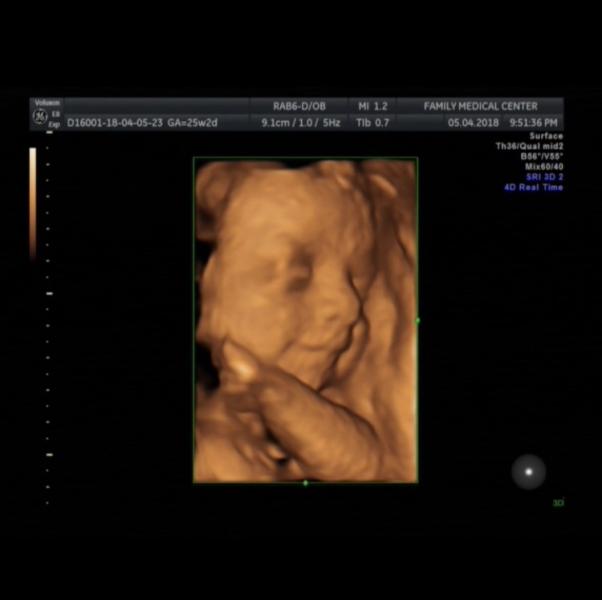

А вот мой сладкий пупсик😍Заждались мы его очень😭А он смеется над нами и даже не думает вылазить😂 #flashmob

@qiyaszadefidan, лицо как будто закрывает))зато дудушку сразу всем показал😂

Ааа,какая улыбашка))))